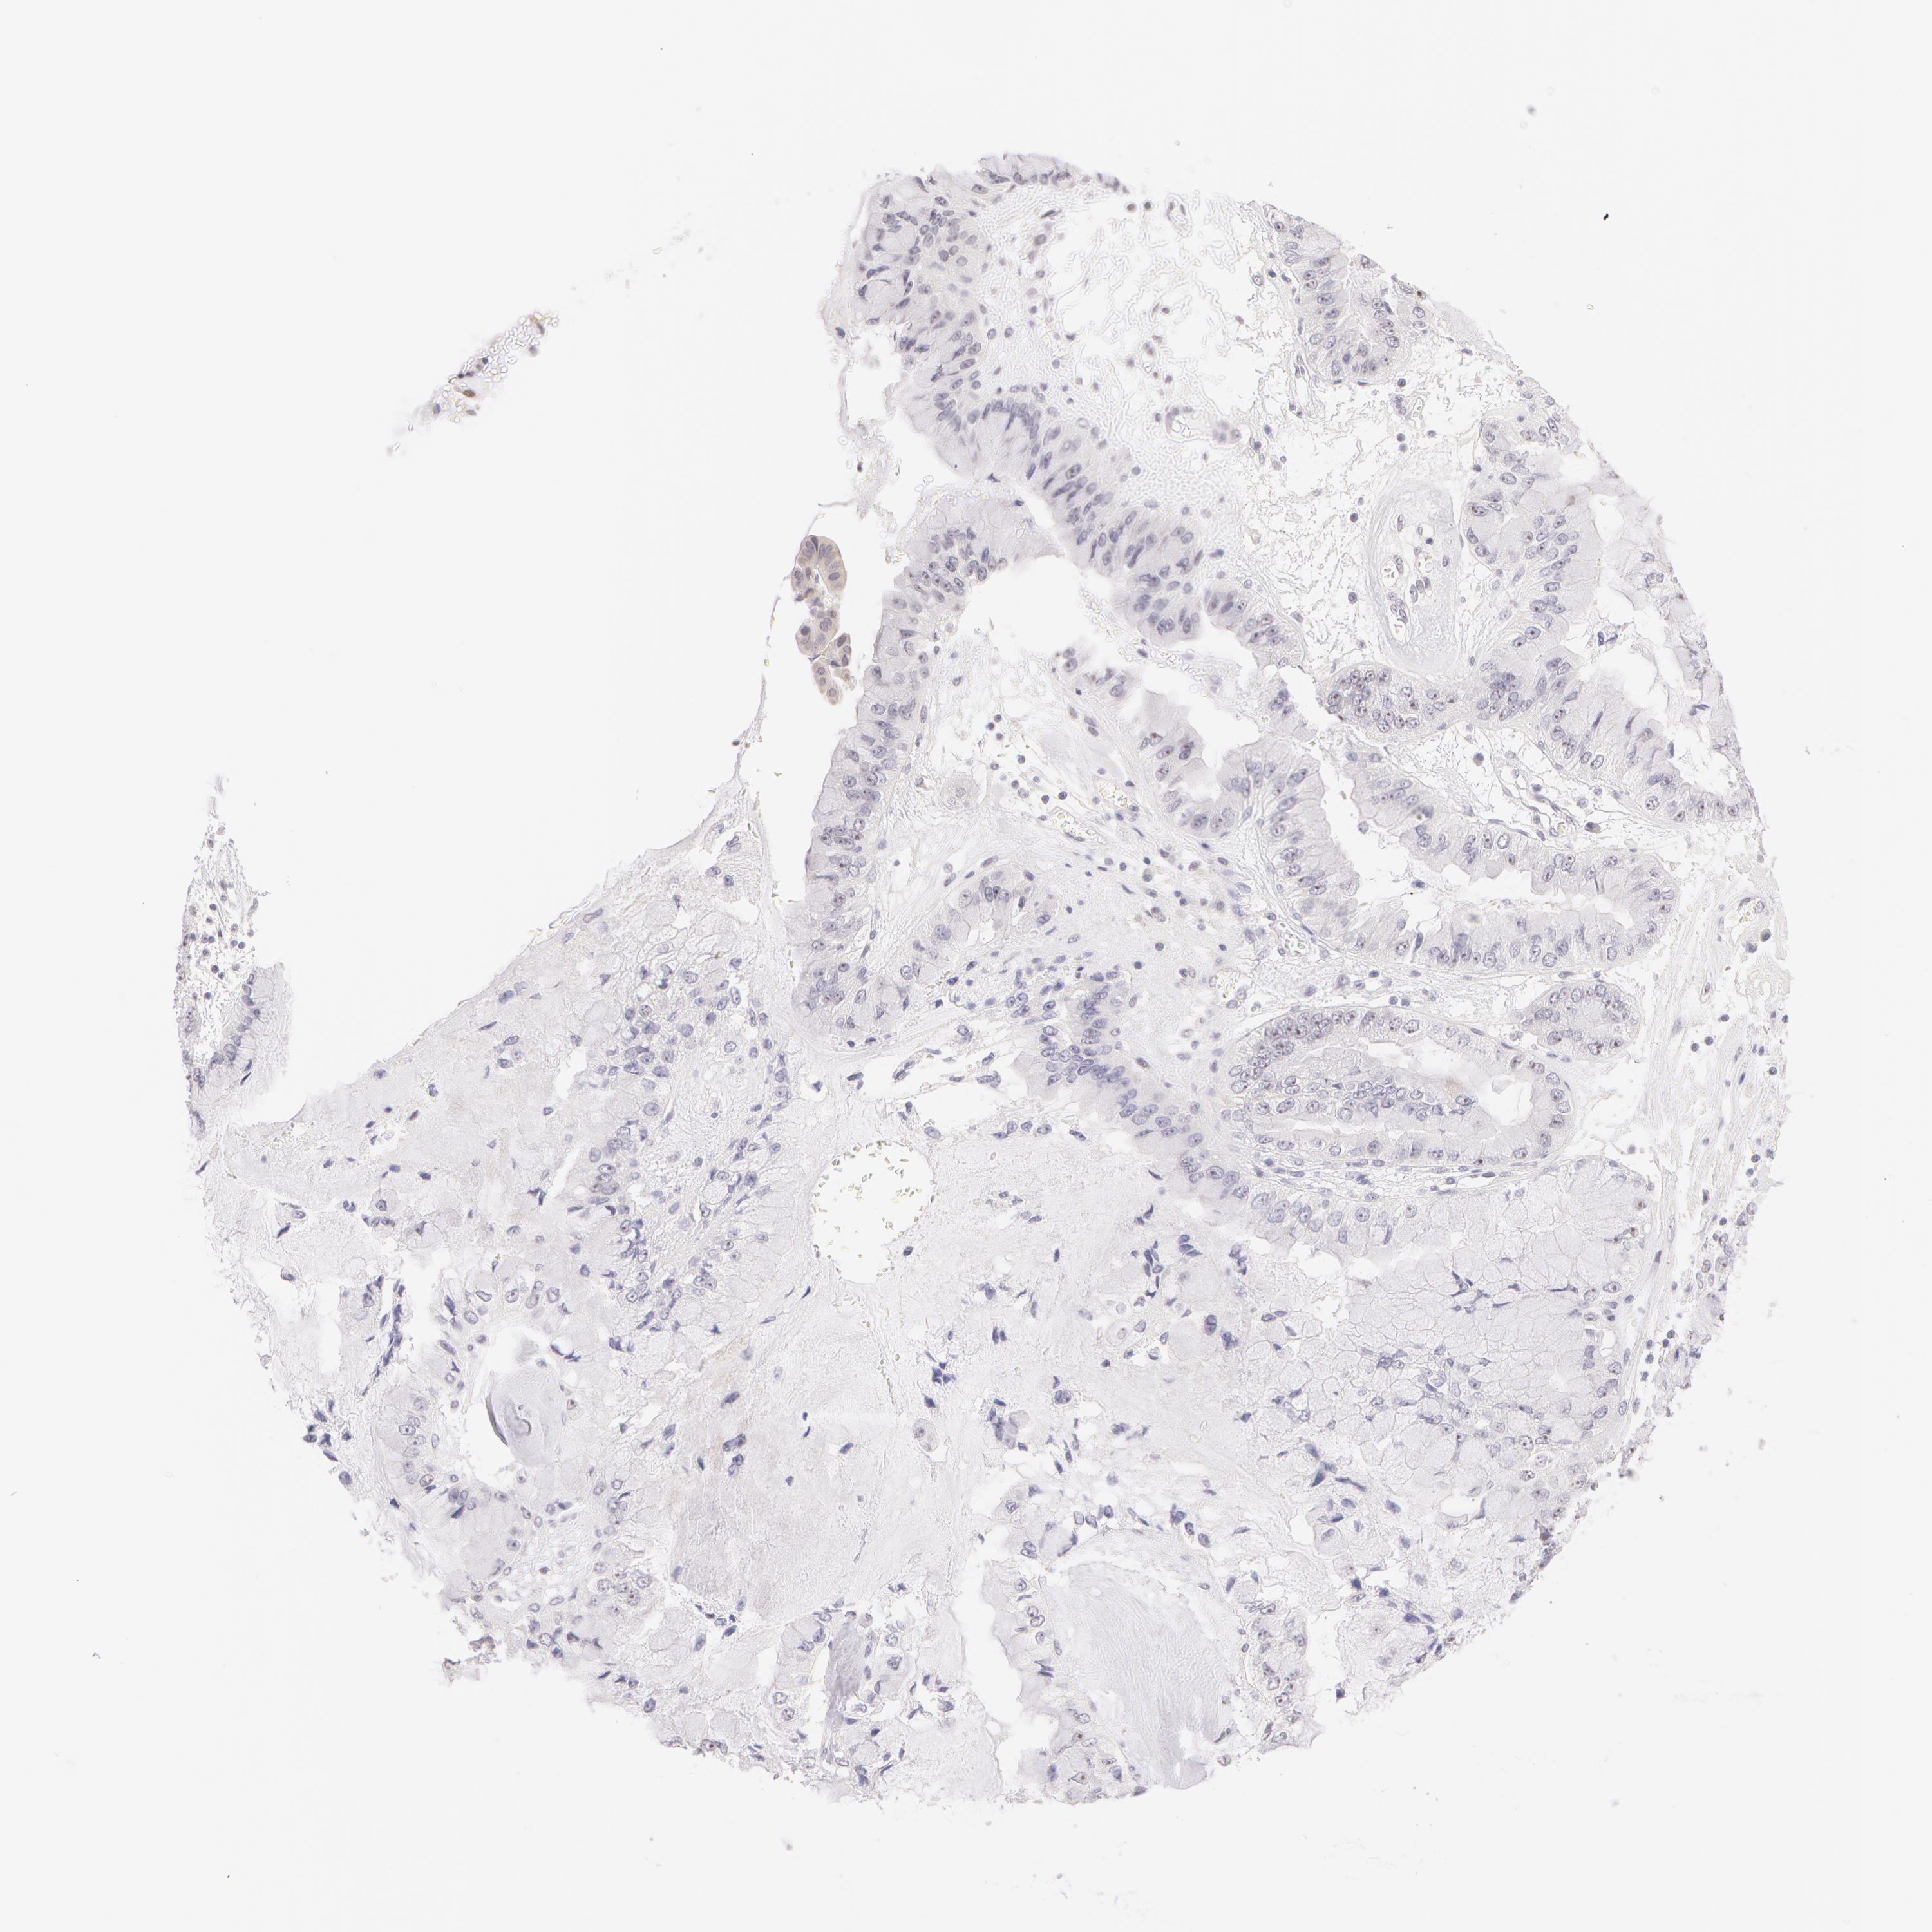

LIVER CANCER - Protein expressioni

A mouse-over function shows sample information and annotation data. Click on an image to view it in a full screen mode. Samples can be filtered based on level of antibody staining by selecting one or several of the following categories: high, medium, low and not detected. The assay and annotation is described here.

Note that samples used for immunohistochemistry by the Human Protein Atlas do not correspond to samples in the TCGA dataset.

Antibody stainingi

Antibody staining in the annotated cell types in the current human tissue is reported as not detected, low, medium, or high, based on conventional immunohistochemistry profiling in selected tissues. This score is based on the combination of the staining intensity and fraction of stained cells.

Each image is clickable and will lead to virtual microscopy that enables deeper exploration of all samples and also displays staining intensity scores, fraction scores and subcellular localization as well as patient and tissue information for each sample.

Antibody HPA001556

Staining

High

Medium

Low

Not detected

Intensity

Strong

Moderate

Weak

Negative

Quantity

>75%

75%-25%

<25%

None

Location

Nuclear

Cytoplasmic/membranous

Cytoplasmic/membranous,nuclear

Carcinoma, Hepatocellular, NOS

Cholangiocarcinoma